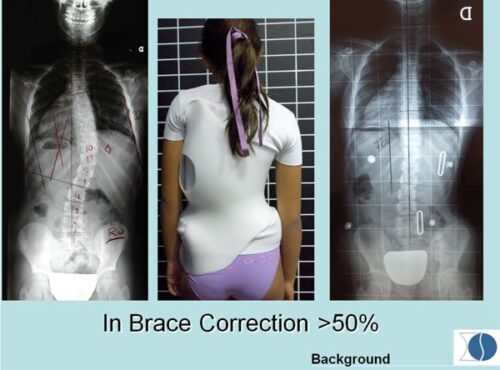

لا يحقق نسبة التصحيح المطلوبة داخل الحزام (In-brace correction).

40–60% تصحيحًا على الأقل داخل الحزام في أغلب الحالات المراهقية.

1) اختيار نوع حزام غير مناسب لنوع الانحناء

بعض الانحناءات تحتاج حزام 3D

3) عدم ضبط نقاط الدفع (Pressure pads)

إذا لم تكن نقاط الدفع موضوعة بدقة على قمة الانحناء، فلن يحدث أي تصحيح.

إجراء أشعة داخل الحزام بعد 2–4 أسابيع من التسليم

إعادة ضبط نقاط الضغط

تعديل القياسات

تغيير الحزام لنوع 3D إذا كان النوع القديم غير مناسب

التطور الكبير في تصميم الأحزمة الطبية جعل علاج اعوجاج العمود الفقري عند المراهقين أكثر نجاحًا وأقل إزعاجًا. باستخدام تقنيات التصوير الثلاثي الأبعاد والمحاكاة الرقمية، أصبح الحزام أكثر خفة وراحة، ويعطي نتائج أفضل في تصحيح الانحناء والتواء العمود الفقري.